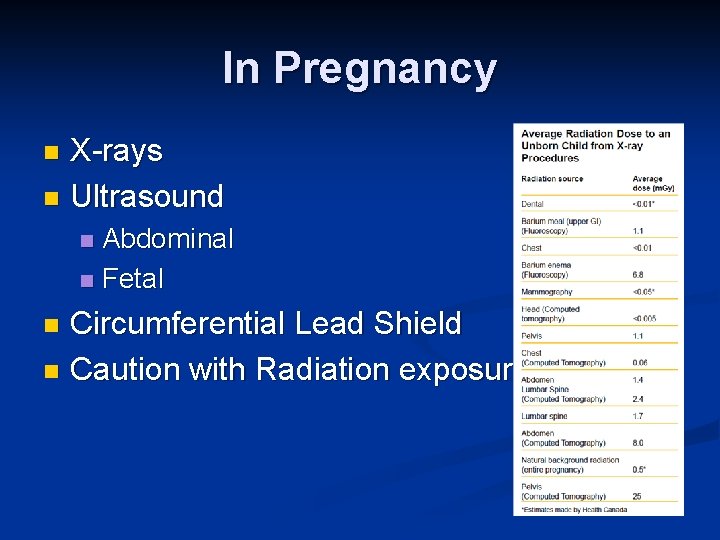

In Pregnancy X-rays n Ultrasound n Abdominal n Fetal n Circumferential Lead Shield n Caution with Radiation exposure n